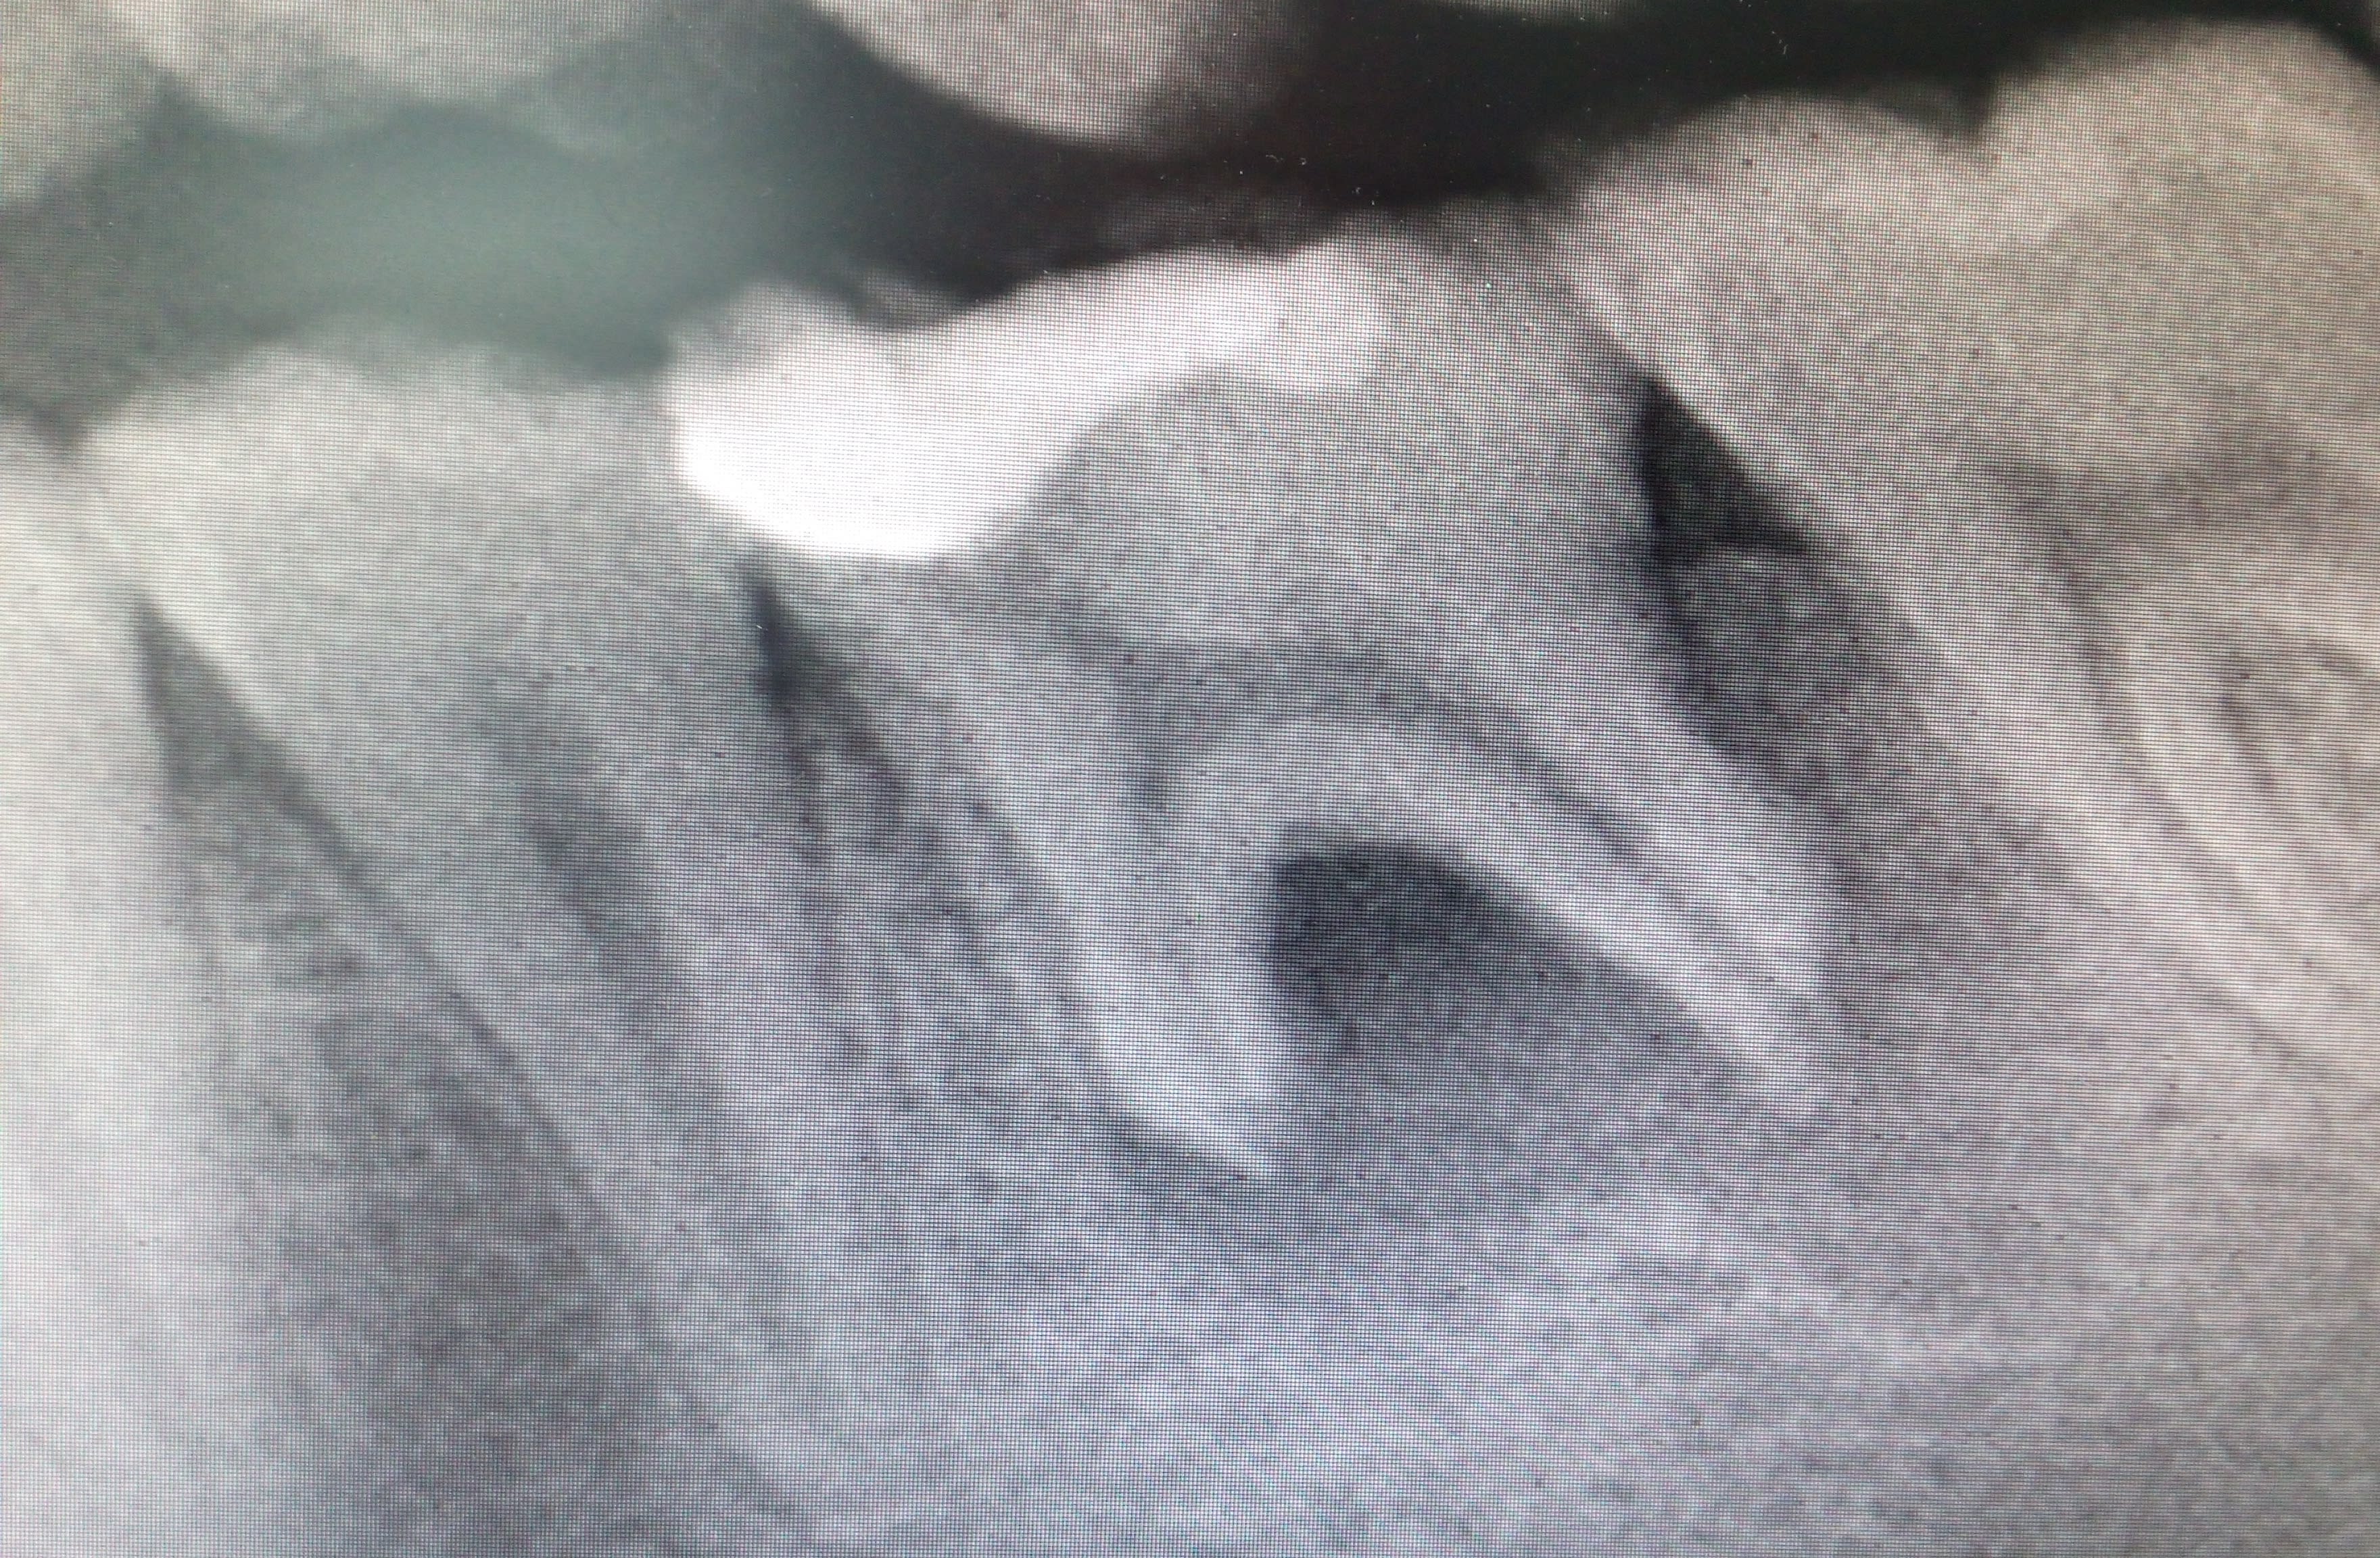

Je me suis rappelé d'un cas similaire que j'avais traité avec une séance d’hydroxyde de calcium, puis obturé tant bien que mal à la gutta. J'ai revu le patient 5 ans après (j'étais collab à l'époque, c'était un patient du titulaire), le TR n'était pas optimal mais le résultat plutôt pas mal.

Je me rappelle également avoir cureté un tissu de granulation au niveau de la furcation en vestibulaire, ce qui à dû aidé à la cicatrisation.

Le patient avait 16 ans, il fallait temporiser.